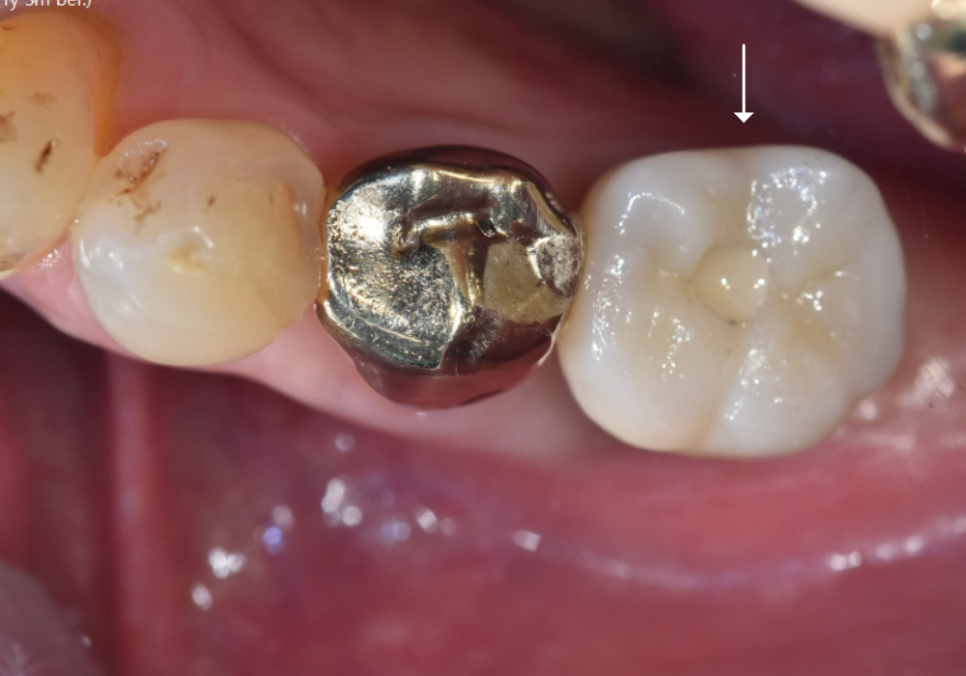

이번에는 반대로 즉시식립이 가능했던

환자분의 케이스를 볼게요.

왼쪽 아래 어금니(#36)를 보시면

뿌리 한쪽이 툭 부러져 있는 모습이에요.

부러진 뿌리 위쪽으로 하얗게 보이는 것이

바로 '포스트(Post)'라고 불리는 기둥입니다.

치아 머리가 많이 손상되었을 때

보철물을 지탱하기 위해 심어두는 기둥인데,

그만큼 치아가 약해져 있었다는 뜻이기도 하죠.

결국 딱딱한 음식을 드시다가

뿌리까지 부러져 내원하셨습니다.